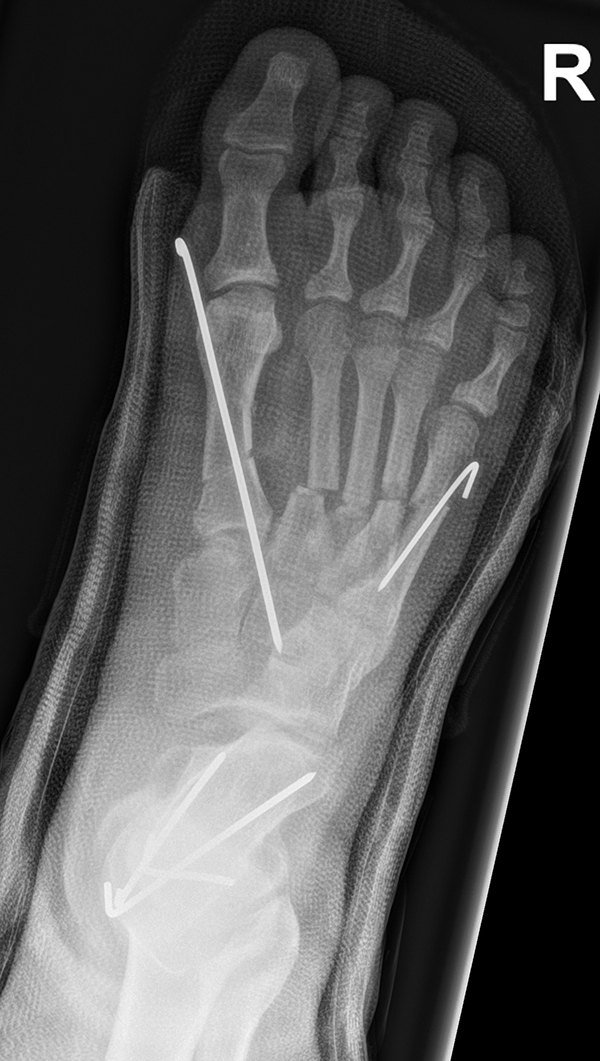

Chevron Osteotomie

Die Chevron Osteotomie 1 ist ohne Komplikationen am wachsenden Skelett durchführbar. Das Metatarsale I besitzt distal keine Wachstumsfuge, die geschädigt werden könnte. Die „französische Methode nach Marc Elkaim“ eignet sich für Kinder ganz besonders (Abb. 28).

Abb. 28 a-g: Radiologischer Verlauf einer Chevronosteotomie nach dem Verfahren von M. Elkaim mit prä- (a-c drei unterschiedliche Ansichten) und intraoperativen Röntgenbildern in zwei Ansichten (d-e) sowie postoperativ zwei Ansichten (f-g).

Zum Lesen der Bildbeschreibung und zur Vollansicht bitte die Bilder anklicken. Bilder: A. Helmers.

Sie wird über eine eigene Tapetechnik fixiert und kann bei einem erhöhten Intermetatarsale-Winkel alternativ zur Scarf-Osteotomie durchgeführt werden. Nachteile der Methode sind eine deutliche Verkürzung durch die Fräse sowie eine starke Plantarisierung des Metatarsale I Köpfchens. Um die Verkürzung zu vermeiden, wird verlängernd in Richtung des Metatarsale II Köpfchens (nicht wie offen in Richtung Metatarsale IV Köpfchen) osteotomiert. Gleiches gilt für die starke Plantarisierung, die durch den Knochenverlust der Fräse entsteht. Die Korrektur eines kindlichen oder jugendlichen Hallux valgus ist mit der Methode ansonsten suffizient durchführbar. Wird verkürzt, muss ausreichend plantarisiert werden, um eine Transfer-Destabilisierung MT II-IV zu vermeiden.

Die MICA-Technik sollte bei geschlossenen Fugen mit einem weitem intermetatarsale Winkel durchgeführt werden. Die dafür typische Verschraubung der Osteotomie kann bei geschlossenen Fugen ohne Probleme erfolgen. Diese Osteotomie kann gut mit einer Akin- und den beschriebenen Kleinzehen-Osteotomien kombiniert werden.